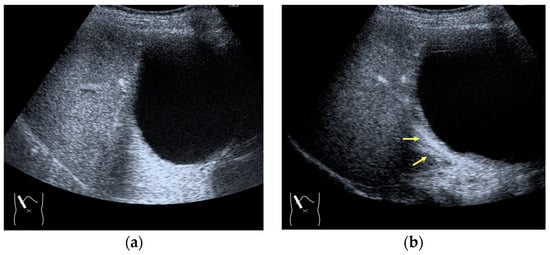

Current US machines reconstruct B-mode US images based on the assumption that sound passes through all parts of human tissues in a straight line and at a constant acoustic velocity (1540 m/s), and this assumption is applied to all scanning planes. The displayed position in a US image usually corresponds with the actual position on the structure. Strictly speaking, however, the acoustic velocity changes according to the tissues [44,45]. Thus, when a plane containing tissues with different acoustic velocities is scanned, sound refraction occurs at the interface between these tissues according to Snell’s law. As a result, the displayed position of point A (the true location) along the line that passes through the interface is falsely displayed at point A’ (a different position) in the B-mode US image as if there was no sound refraction. This refraction artifact is clearly seen in a cirrhotic liver (Figure 3), around a round mass (e.g., a hepatic cyst) (Figure 4) and below the rectus muscles in the transverse scanning plane of the upper abdomen (Figure 5). We will now provide a brief explanation for these three artifacts (Figure 3, Figure 4 and Figure 5). In macronodular liver cirrhosis, sound refraction occurs at the irregular hepatic surface, resulting in the improper positioning and display of echo brightness in the US image [44,45,46], giving the appearance of a “tricolor flag” [46] (Figure 3). When a US beam passes through a mass with an acoustic velocity different from that of the surrounding hepatic parenchyma, it changes direction twice due to sound refraction, first at the liver parenchyma–mass lesion entrance interface and again at the mass lesion–liver parenchyma exit interface. The liver structure behind the mass lesion thus appears to be deformed in B-mode US and heterogeneous in CEUS (Figure 4). As has been reported, sound refraction occurs most clearly at both edges of a mass lesion, and the degree of sound refraction is nearly proportional to the incidental angle of the US beam striking the liver parenchyma–mass lesion interface. Globally speaking, the degree of sound refraction is accentuated as the US beam strikes peripheral to the mass lesion. This is why the posterior echo behind the mass lesion is not homogeneous, as observed in Figure 4. In the transverse scanning of the upper abdomen, the US beam is largely refracted, first at the anterior wall of the rectus muscles and then at the posterior wall of the muscle (Figure 5c). As a result, the liver below the rectus muscles is more or less deformed in B-mode US and CEUS, as seen in Figure 5a,b. The most useful prevention strategy is to use the reference B-mode image (the so-called dual-image technique), which allows for a simultaneous comparison between the CEUS and B-mode images.

Figure 3.

Refraction artifact (1): many vertical bands of different echogenecities in macronodular cirrhosis. (a) Gray-scale US reveals that the left hepatic lobe is markedly deformed with an irregular surface. The liver gives the appearance of a tricolor flag. (b) CEUS shows the liver to be composed of many vertical bands of different brightness (arrows), giving the appearance of a tricolor flag.